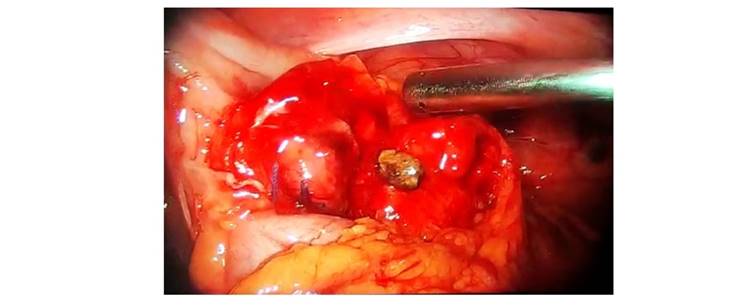

El 20 de octubre (día 4) se intervino nuevamente a la paciente, se realizó una laparoscopía diagnóstica, donde se observó líquido seropurulento de aproximadamente 280 cc en fondo de saco de Douglas, parietocólico derecho y subfrénico derecho, múltiples adherencias en cuadrante inferior derecho, apéndice cecal con muñón indemne con 1 coprolito en su interior, el cual fue extraído (Figura 2).